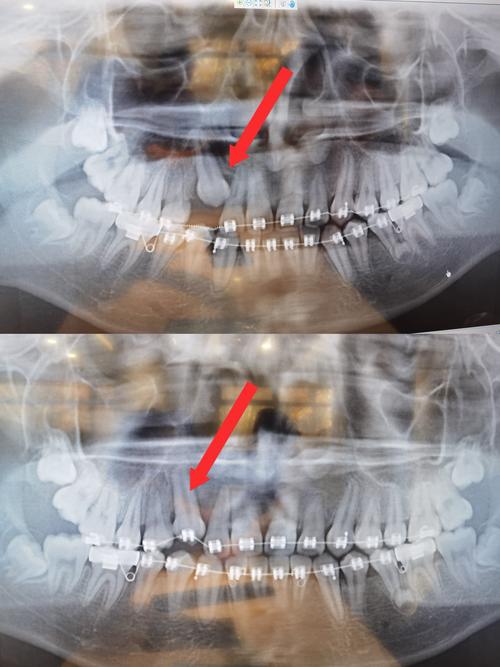

通过X线片(曲面断层、头颅侧位片)评估牙根位置、牙槽骨高度及密度,排除牙根吸收、骨粘连等禁忌证;模型分析测量覆合、覆盖程度,计算压低量;设计支抗方案(如颌内支抗、腭杆、种植体支抗等),确保后牙支抗稳定,避免压低过程中后牙前移或伸长。

每4-6周复诊一次,临床检查牙齿压低量、咬合变化及牙周反应(牙龈红肿、松动度),拍摄X线片观察牙根位置及牙槽骨改建情况;若压低过快导致牙根吸收风险,需暂停加力,改为保持弓丝稳定;若支抗丧失(如后牙前移),需加强支抗装置(如增加种植体支抗)。